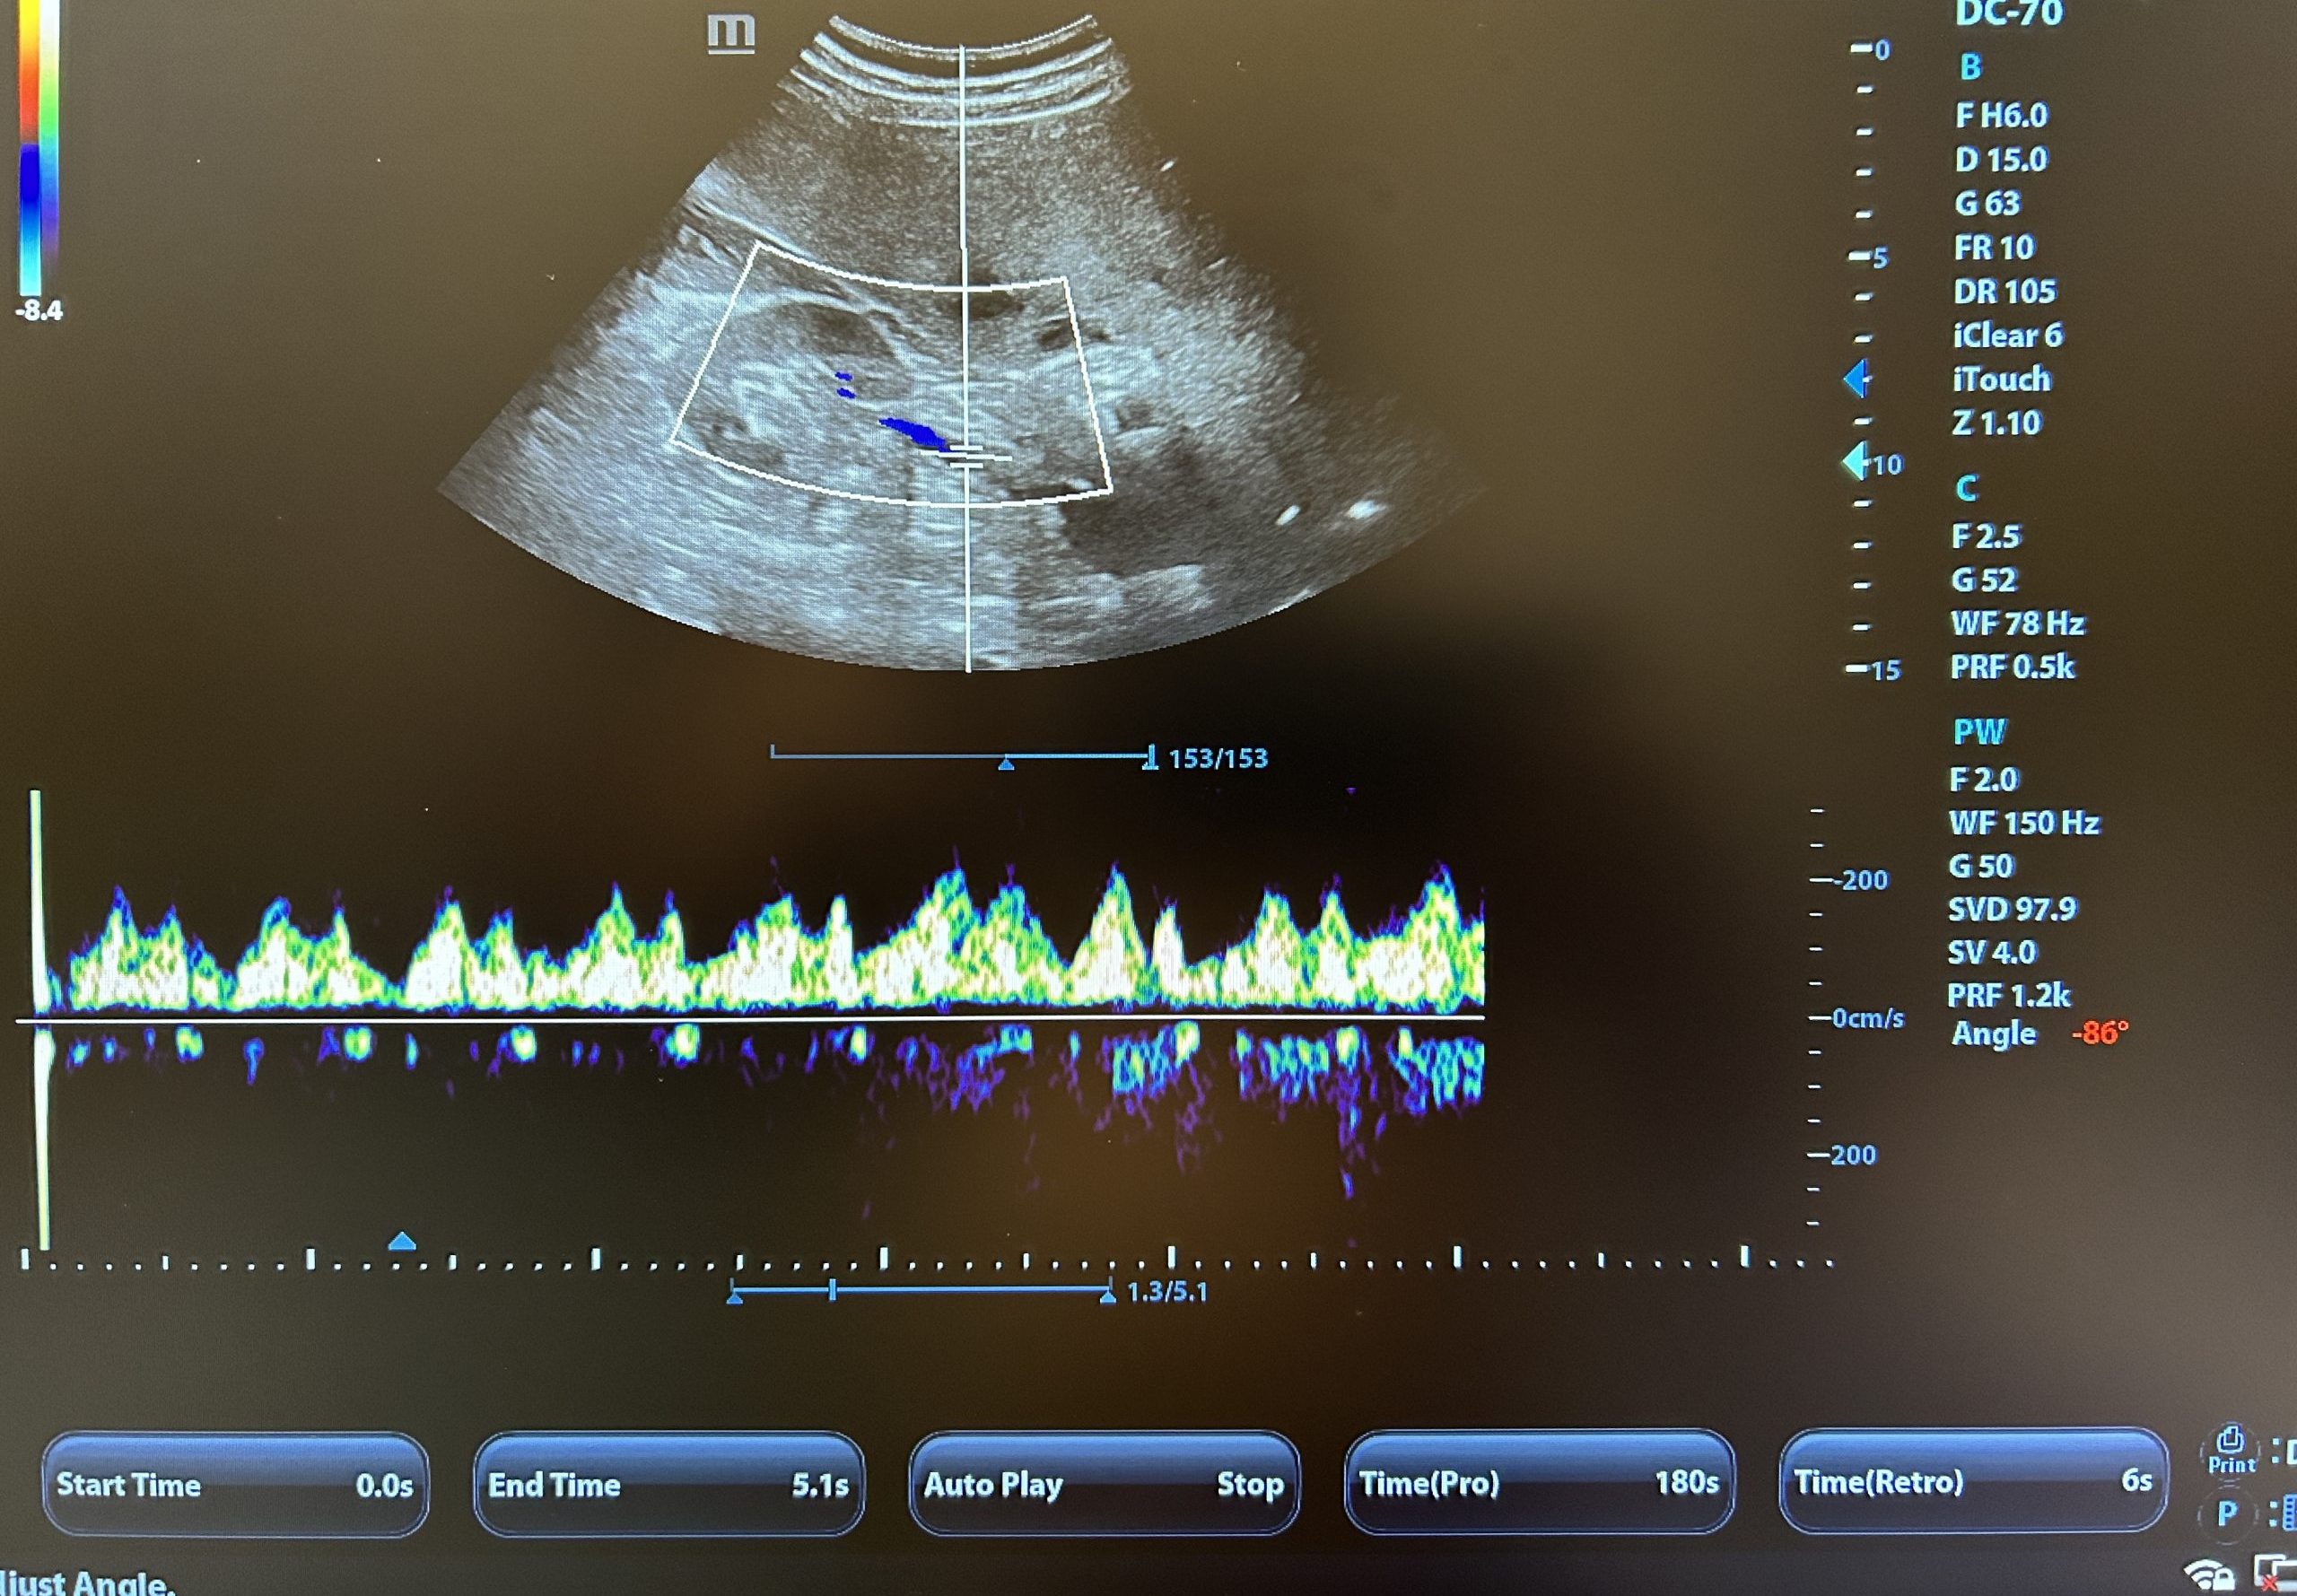

- SP5-1N — фазированный датчик для ЭХО и брюшной области

- P8-2 — основной кардиологический датчик для TDI, AutoEF, Stress Echo

- P7-3Ph — карандашный CW-допплеровский датчик (непрерывный допплер)